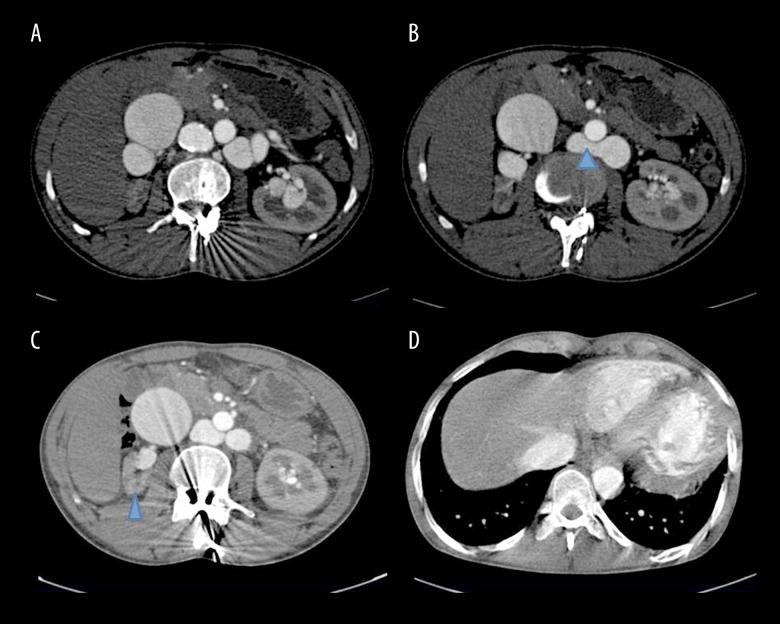

A 29-year-old male presented to the cardiology department with complaints of breathlessness, abdominal pain and hematuria for the last 6 months. On clinical examination there was evidence of audible bruit over the abdomen. He had a past history of a gunshot injury around two years back. CT angiography revealed a large partially calcified pseudoaneurysm arising from the right lateral wall of the abdominal aorta with the neck of the pseudoaneurysm at juxtarenal location with a fistula between the anterior wall of the pseudoaneurysm and the posterior wall of the right renal vein. There was an associated incidental finding of circumaortic left renal vein with gross aneurysmal dilatation of both pre- and retro-aortic part of the renal vein.

Delayed presentation of aortic pseudoaneurysm with its fistulous communication with the right renal vein is a rare entity. CT angiography is a non-invasive modality for diagnosis of the exact site of communication, length of aneurysm, proximal and distal extent of the affected segment and its relationship with surrounding structures.